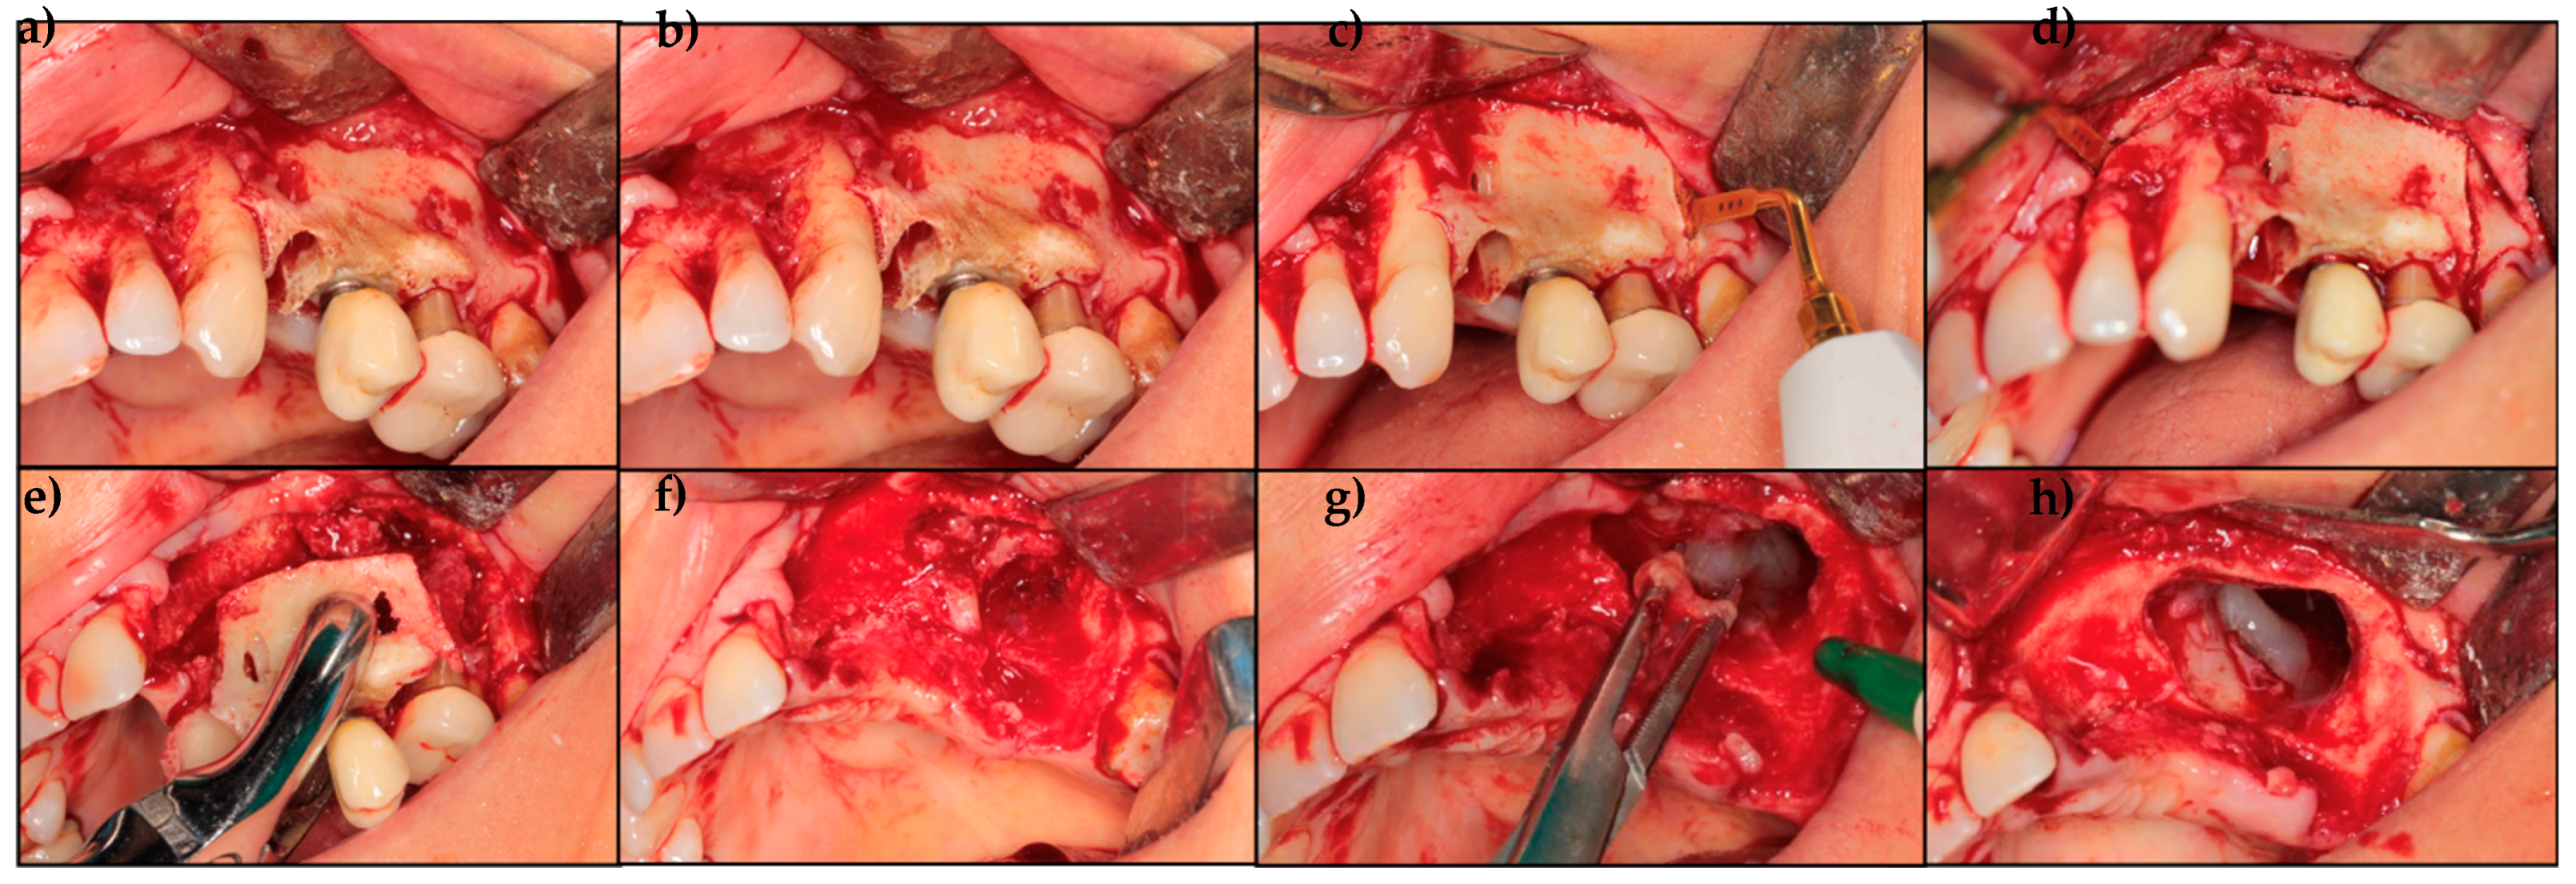

Treatment Protocol

- If complete healing is not achieved, patients are treated with surgical laser assistance.